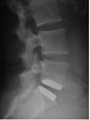

- In allen anderen Fällen wird durch einen kleinen Hautschnitt von 2-3 cm der Wirbelkanal dargestellt.

- Unter dem Operationsmikroskop wird der Nerv weggehalten und das herausgesprengte Bandscheibenmaterial entfernt.